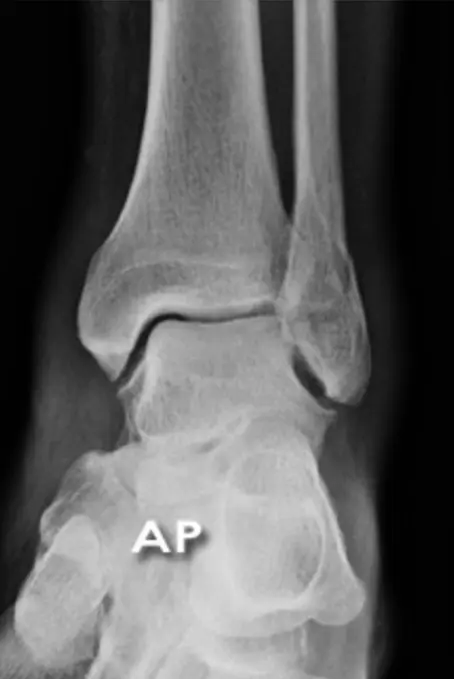

x-ray lat. view of ankle joint

- The image presents two X-ray views of an ankle joint.

- The left image is a plain X-ray.

- The right image is a labeled version of the same X-ray.

Labeled Components:

- Bones:

- tibia

- fibula

- talus

- navicular

- cuboid

- calcaneus

- MT5 (Fifth Metatarsal)

- Other Structures:

- achilles tendon

- Kagerâs Fat Pad

- Joints:

- subtalar joint

- Other:

- mal. tertius

Patient: 32âyearâold male with a severe twisting ankle injury â painful, swollen and unable to stand.

Findings

- Site: lateral malleolus

- Fracture type: simple

- Fracture line: spiral

- Displacement: gap medially

- Special issue: possible ruptured deltoid ligament